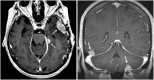

Methods: Patients with brain metastases, of which 1 was resected and treated with adjunctive SRS, and who subsequently developed LMD were combined from 7 tertiary care centers. LMD pattern was categorized as nodular (nLMD) or classical ("sugarcoating," cLMD).

Conclusions: Nodular LMD is a distinct pattern of LMD associated with postoperative SRS that is less likely to be symptomatic and has better OS outcomes than classical "sugarcoating" LMD. Although focal RT demonstrated increased second LMD recurrence compared with WBRT, there was no associated OS detriment. Focal cranial RT for nLMD recurrence after surgery and SRS for brain metastases may be a reasonable alternative to WBRT.